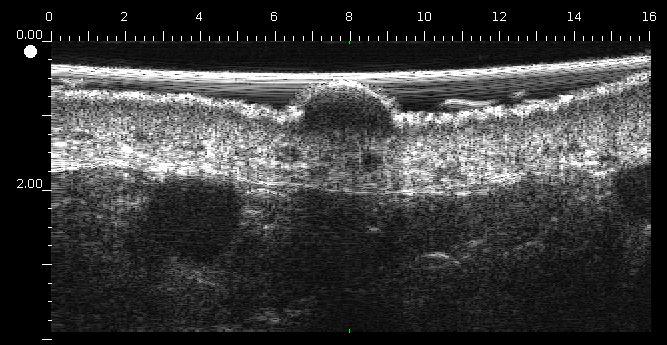

Quiste epidérmico

Lesión hipoecoica de forma redonda, bien definida con ecos centrales muy densos paralelos a la superficie